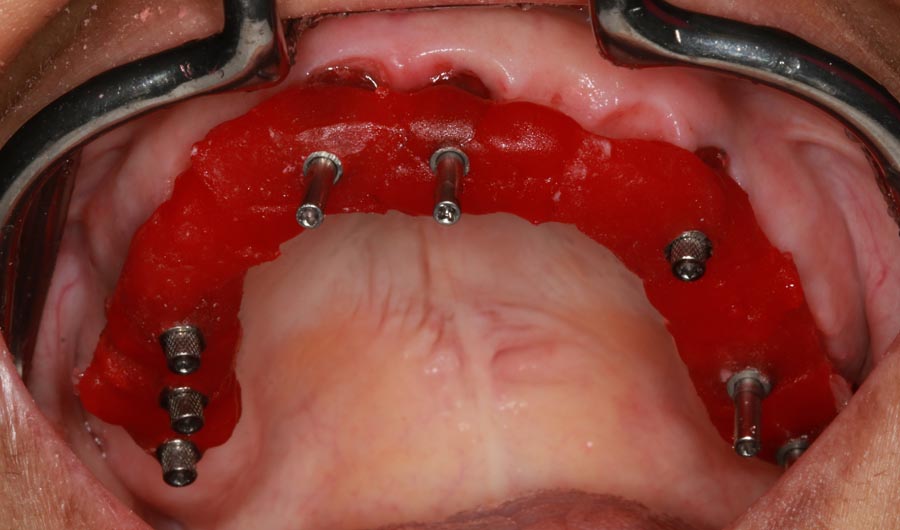

Smile GalleryImplant RestorationsFull Mouth Implant Restoration Full arch zirconia implant bridge (full smile) 1 of 37 Pre-op full smile Pre-op lips retracted Pre-op panoramic x-ray Extraction of strategic teeth Placement of implants Extraction of some remaining teeth after verification of adequate implant stability Occlusal view Post-op panoramic x-ray Immediately fabricated provisional restoration (tissue side view) Immediately fabricated provisional restoration (occlusal side view) Immediate provisional delivered on day of surgery Immediate provisional 2 weeks later Scalloped tissue developed from the provisional at 2 weeks Jig used for making a master impression Provisional in place (full smile) Provisional in place (lips retracted) Provisional in place (right side) Provisional in place (left side) Wax try-in (full smile) Wax try-in (right side full smile) Wax try-in (left side full smile) Wax try-in (full face, lips together) Wax try-in (full smile) Wax try-in (right side) Wax try-in (left side) Wax try-in (lips retracted) Full arch zirconia implant bridge on master cast (frontal view) Full arch zirconia implant bridge on master cast (occlusal view) Implant positions and soft tissue representation on master cast (occlusal view) Soft tissue representation on master cast (frontal view) Full arch zirconia implant bridge (tissue side view) Soft tissues on day of delivery (occlusal view) Soft tissues on day of delivery (frontal view) Full arch zirconia implant bridge delivered (lips retracted) Full arch zirconia implant bridge (lips retracted, close up) Post treatment panoramic x-ray Full arch zirconia implant bridge (full smile)